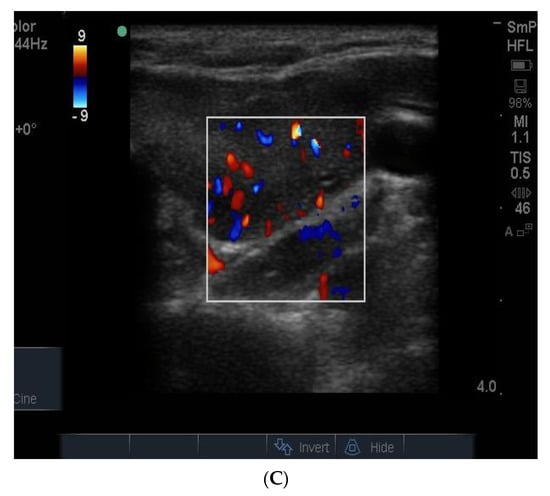

The blood supply to thyroid nodules is an important feature to be documented in the course of real time ultrasonography. There are three types of vascularity to be discussed. Firstly, the so-called hypoechoic halo surrounding a benign nodule is caused by compressed blood vessels which can be seen when the “colour” button is engaged. An example of this is seen in Figure 9A. Secondly, the degree of vascularity around the outside of a nodule is reflective of its activity and prominent blood supply around a nodule maybe a sign of thyroid cancer (Figure 9B) [] but can also be present around nodules shown by biopsy to be benign. It has recently been shown that blood vessels within a nodule, especially if it has other suspicious features (Figure 9B), may be a reliable sign of cancer [].

Figure 9.

Examples of vascularity around the edge of a benign nodule and (A) associated with blotchy macrocalcifications in a hard, irregular edged nodule that is suspicious for papillary cancer (B). Another example of macrocalcifications in papillary thyroid cancer.

In Figure 10 is shown matching images of a benign nodule without (A) and with (B) blood flow in the halo around the nodule.

Figure 10.

A small 8 mm benign nodule in the left thyroid lobe shown as an ultrasound image (A) and with surrounding vascularity in (B).